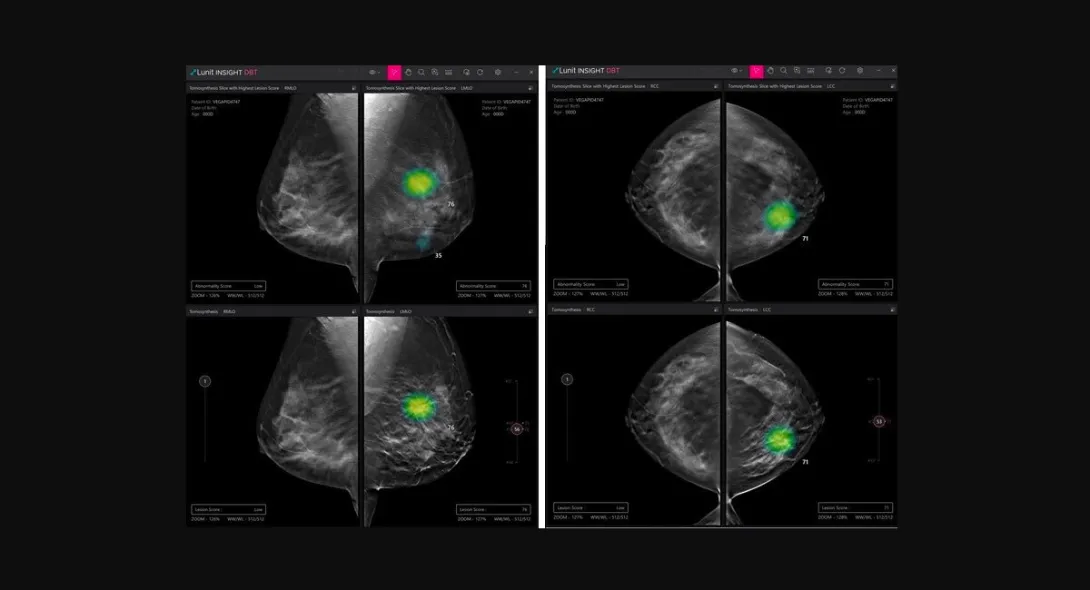

Lunit obtains new CE mark for AI DBT solution

South Korean medical AI company Lunit has received a CE mark under Europe's latest Medical Device Regulation for its AI software for digital breast tomosynthesis (DBT) analysis.

Called Lunit INSIGHT DBT, the software solution analyses 3D images from DBT, enabling fast and accurate diagnosis of breast cancer.

In a press statement, Lunit disclosed its plan to start rolling out the software product in Europe by the end of March, noting an uptick in interest. It also announced its plan to begin the process of acquiring the US FDA's approval for Lunit INSIGHT DBT in the third quarter. The technology has already been approved for commercialisation in South Korea early this year.